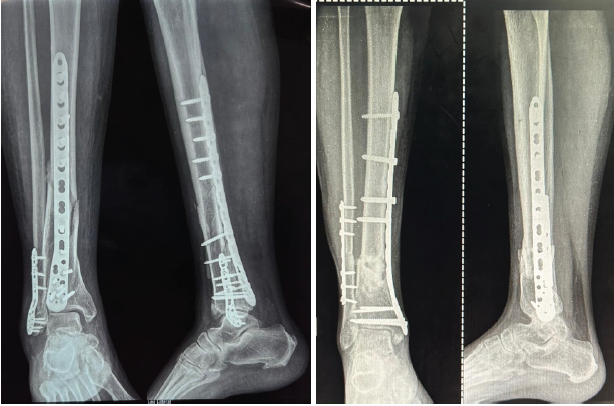

Functional outcomes were assessed using the American Orthopaedic Foot and Ankle Society (AOFAS) Ankle–Hindfoot Score at 2, 4, and 8 weeks [25]. Radiological union and alignment were evaluated at 2, 4, 8 weeks, and 6 months (Figure 1). Complications such as infection, delayed union, and implant irritation were recorded [26].

Figure 1: Representative post-operative radiographs showing posterior plating (left) and medial plating (right) with maintained alignment at 6 months.